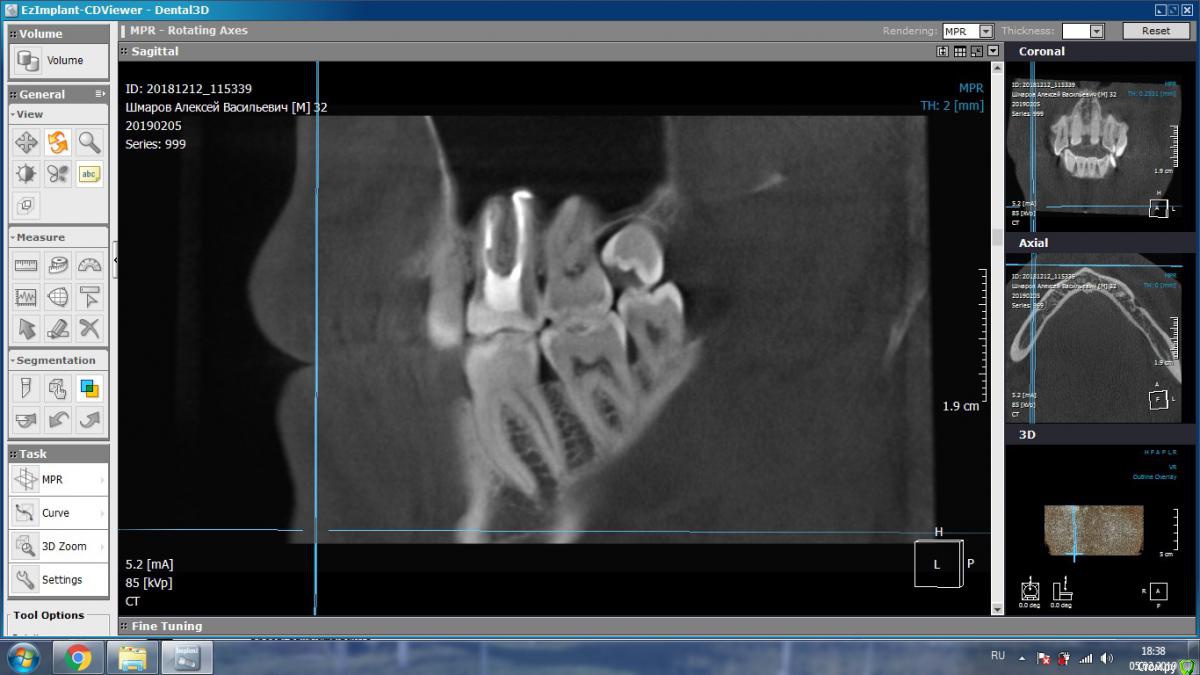

aleks.k Опубликовано 5 февраля, 2019 Автор Поделиться Опубликовано 5 февраля, 2019 Добрый день! Сделал КТ. Посмотрите пожалуйста.Есть 2 мнения очных стоматологов, пока никто из них КТ не видел, мнение на основании предыдущего панорамного снимка:1. Надо удалять 6 зуб справа2. Который и депульпировал 6 зуб сказал, что проблемы в 6 зубе нет, зуб мудрости нужно оттянуть брекетами. Размер файла 131 мб. http://fayloobmennik.cloud/7349278 Ссылка на комментарий

aleks.k Опубликовано 5 февраля, 2019 Автор Поделиться Опубликовано 5 февраля, 2019 Такие подойдут? Ссылка на комментарий

kramer Опубликовано 5 февраля, 2019 Поделиться Опубликовано 5 февраля, 2019 Судя по срезам, вероятнее причина в пульпите 7 зуба, возникшего в результате давления на него 8-ки. Ссылка на комментарий

aleks.k Опубликовано 6 февраля, 2019 Автор Поделиться Опубликовано 6 февраля, 2019 Срезы Ссылка на комментарий

aleks.k Опубликовано 6 февраля, 2019 Автор Поделиться Опубликовано 6 февраля, 2019 Еще один срез, может быть более удачный чем первые в этой проекции Ссылка на комментарий